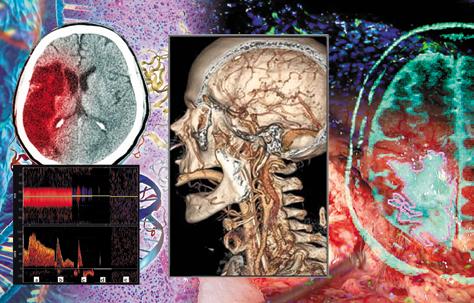

Por ello es que, para establecer el diagnóstico de muerte encefálica en nuestro país, debemos basarnos en lo estipulado en dos documentos que tienen el valor jurídico y legal para llevar a cabo todo el proceso conforme a derecho y dentro de los lineamientos éticos pertinentes. Uno de los documentos es la Ley General de Salud en sus artículos 343, 344 y 346, donde se establece lo necesario desde el punto de vista legal para la certificación de la pérdida de la vida a través del diagnóstico de muerte una imagen cerebral (por lo menos una tomografía de cráneo en fase simple) que muestre la causa de la muerte encefálica (edema cerebral grave, herniaciones, hemorragias graves, etc.).

●Los pacientes con imagen normal deben ser investigados en forma exhaustiva acerca de la causa del daño cerebral (punción lumbar, imágenes funcionales, electroencefalograma, angiografía, etc.).

•A nivel del mesencéfalo: Pupilas con falta de respuesta a la luz y con posición media con tamaño de 4 a 9 mm. La decorticación debe estar ausente. ►Una vez establecido el diágnostico clínico de la muerte encefálica es importante que los hallazgos sean corroborados por estudios de gabinete como lo indica el artículo 344 de la Ley General de Salud, en donde se solicita realizar un electroencefalograma (EEG), o bien, realizar un estudio que demuestre ausencia de flujo encefálico arterial, de los cuales el más utilizado es la angiografía por tomografía computada.

Ambos son accesibles, rápidos, de costo moderado y que permiten confirmar el diagnóstico para, de así requerirlo, continuar con el proceso de donación. La utilización de uno u otro dependerá de la disposición de estos en las unidades hospitalarias y de las condiciones de cada paciente.